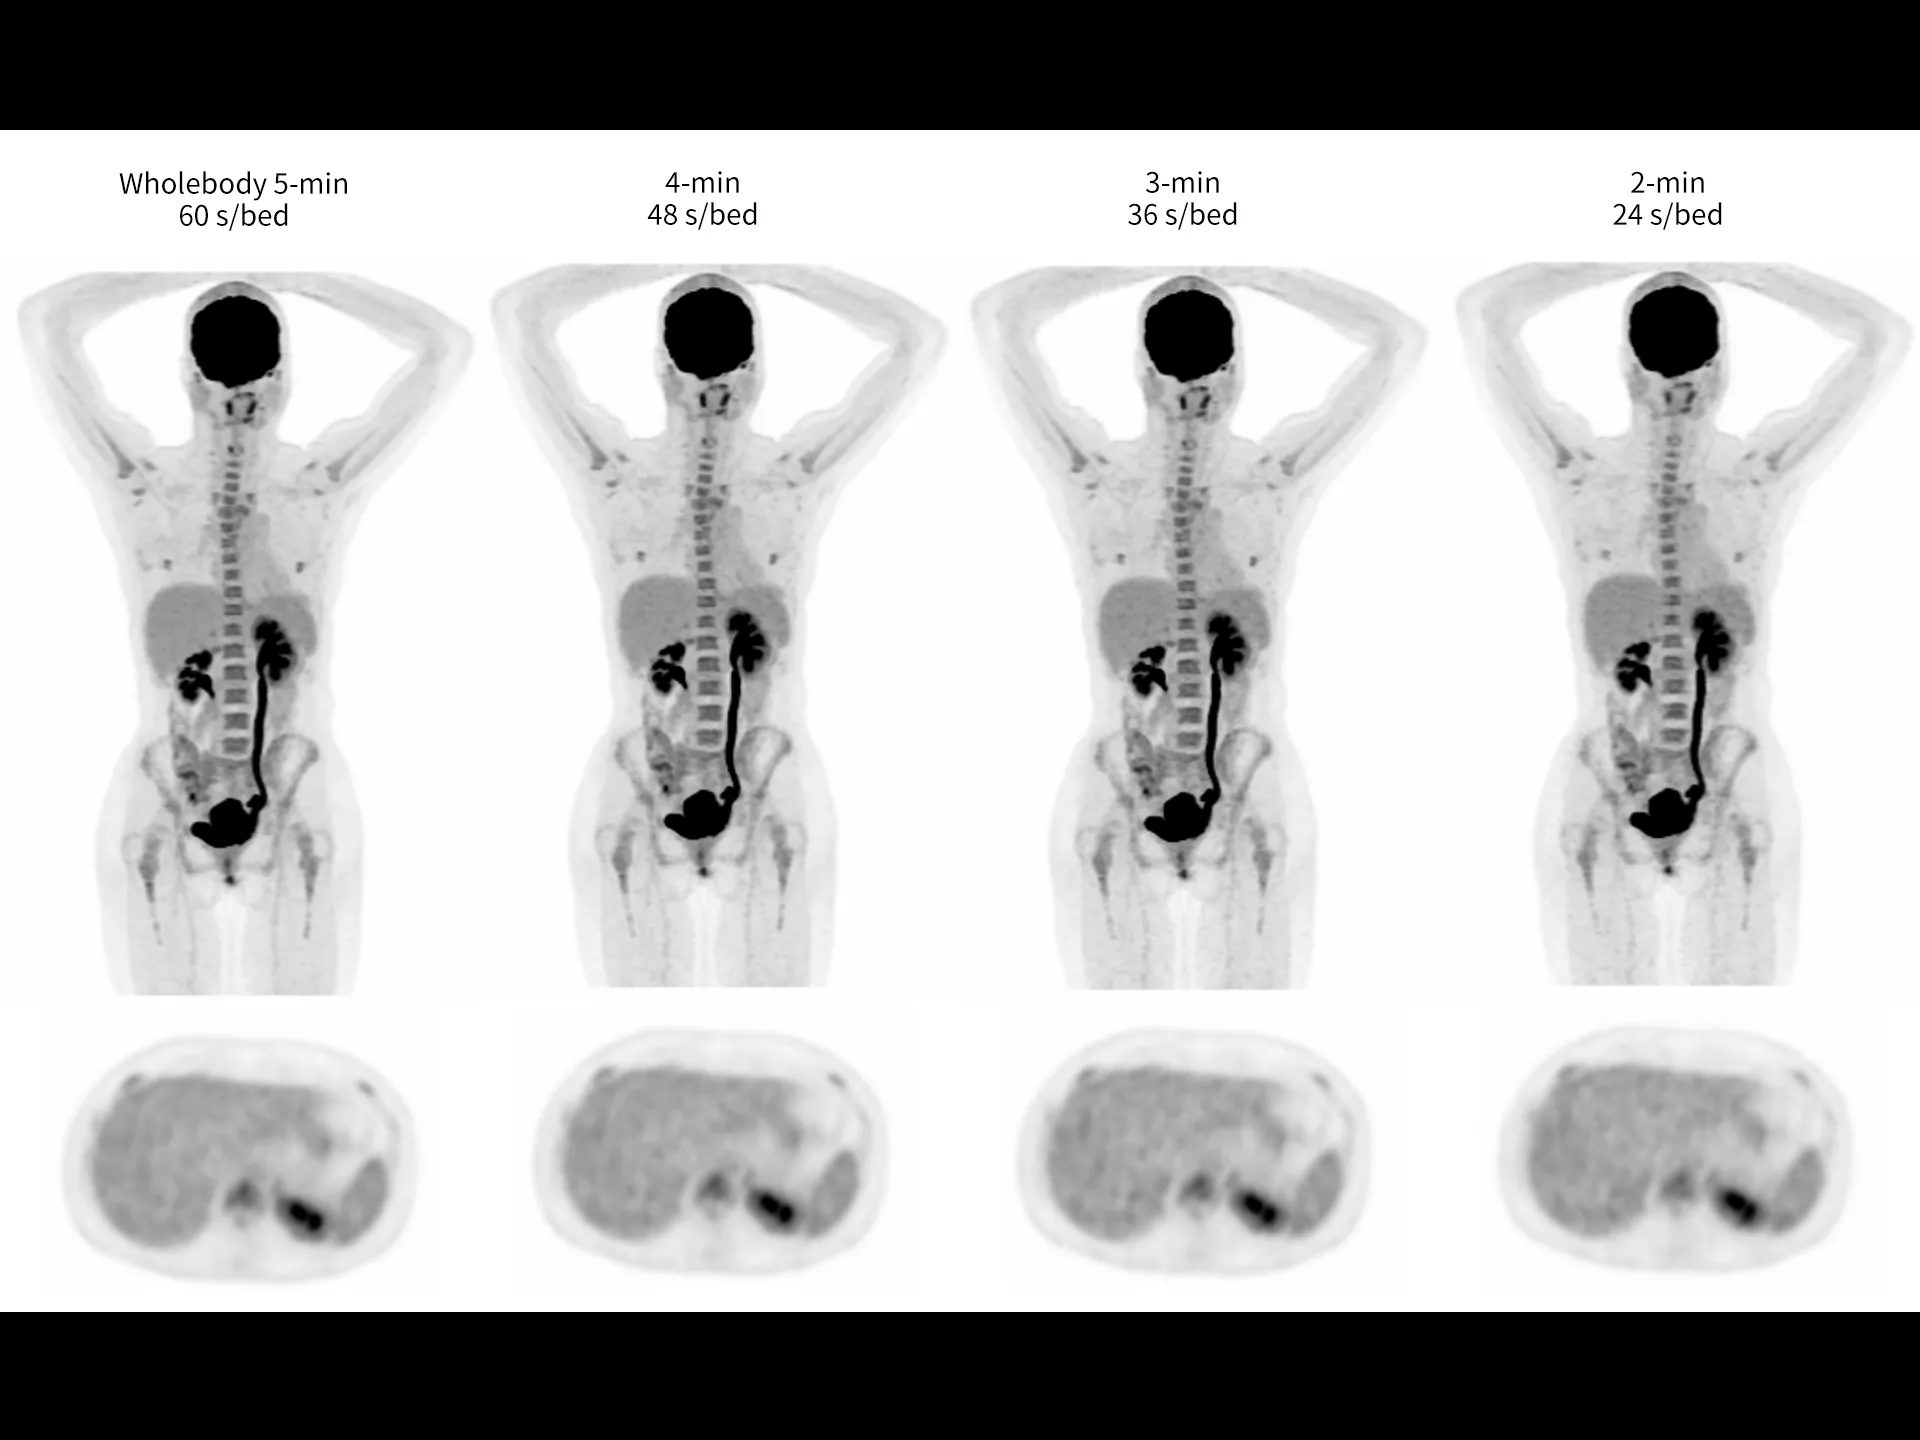

uMI Panvivo is a high performance PET/CT platform that moves state-of-the-art innovative advancement to clinical reality. It advances diagnostic precision with industry-leading NEMA spatial resolution of 2.9mm and time of fight (TOF) timing resolution of 219 picosecond (ps), while it’s air-cooled compact design make it more accessible to all. The human-centric design and fully AI-empowered workflow of uMI Panvivo deliver care to every patient while keeping the user in mind. Built on its scalable platform, uMI Panvivo’s powerful design builds the bridge toward long-term and sustainable success.

Leading TOF resolution that boosts small lesion detectability and clarity.

High effective sensitivity that benefits from TOF gain leverages better diagnostic accuracy under low dose usage and fast scan time.